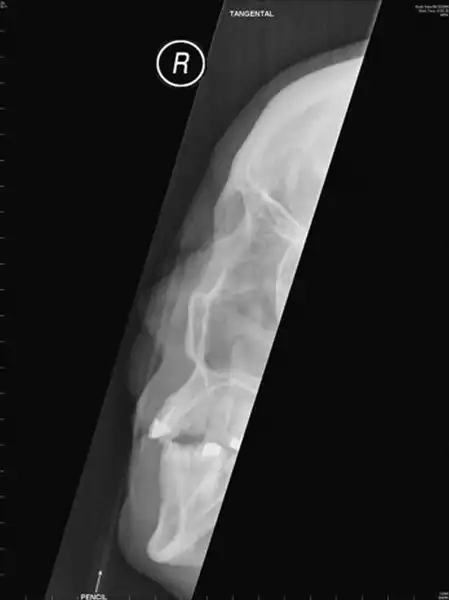

Порой подушка безопасности может нанести немалый ущерб вместо того, чтобы спасти жизнь водителю. Эта 42-летняя женщина пострадала в лобовом столкновении с другим автомобилем на скорости около 50 км/ч. Подушка безопасности сработала как часики, вот только вдобавок резко вытолкнула карандаш, который женщина держала в нагрудном кармане. Канцелярский предмет пронзил ей щеку и веко. К счастью, все обошлось, и глаз удалось сохранить.